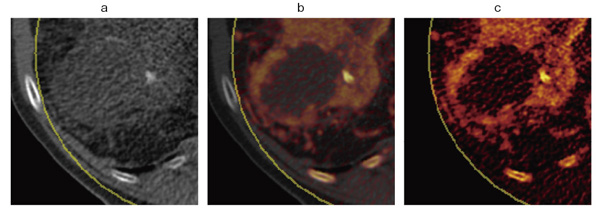

図3 Dual EnergyイメージングによるLiver VNC

Dual Energyモードで撮影を行い,Liver VNCアプリケーションにて作成された仮想的な非造影の画像(a)である。造影剤の比率を50%(b),100%(c)と変化させることで,壊死部を除いた全体が強い濃染を示していることが明瞭となり,Necrotic Tumorであることがわかる.さらに,壊死部の領域・境界も明瞭に把握可能である。

〔画像ご提供:ミュンヘン大学様(ドイツ)〕